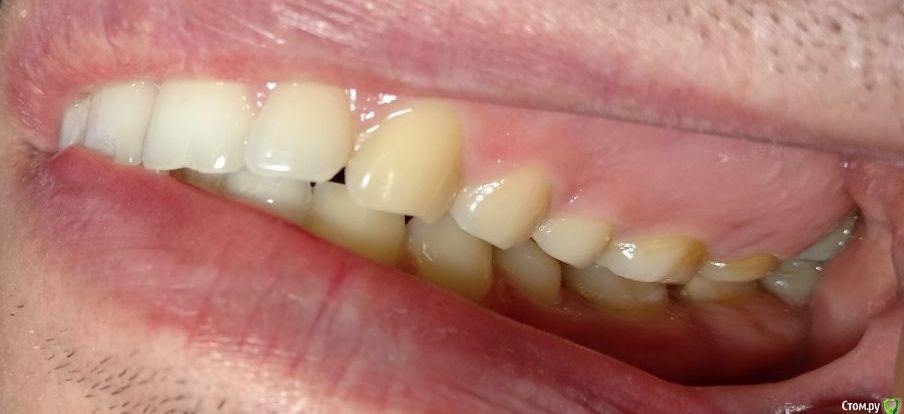

Нормально вылечены каналы. Покажите фото сомкнутыми зубами

Сделал несколько фотографий, тк не совсем понял с какого ракурса делать фото с сомкнутыми зубами.